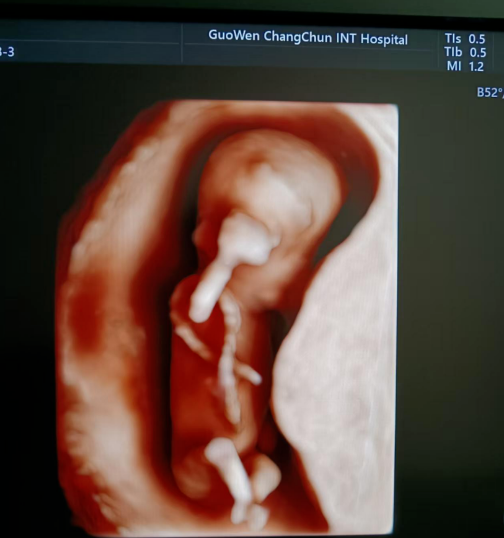

寶媽看過來! 胎兒NT彩超免費檢查長春國文醫(yī)院支持國家優(yōu)生優(yōu)育政策,回饋寶媽,NT彩超檢查免費。那么,什么是NT檢查呢?

NT 檢查是一種在孕期進行的重要檢查項目,全稱為頸項透明層檢查,以下是關于它的詳細介紹:

通常在懷孕 11 周 - 13 周 + 6 天之間進行。這個時期胎兒大小適中,頸項透明層的顯示較為清晰,測量結果也相對準確,能更好地發(fā)揮 NT 檢查對胎兒異常的篩查作用。

超聲檢查,孕婦無需空腹。檢查時,超聲醫(yī)生會使用超聲儀器對胎兒頸部進行仔細觀察和測量。通過超聲探頭可以清晰地看到胎兒在子宮內(nèi)的情況,重點測量胎兒頸項部皮下無回聲透明層最厚的部位,測量值即為 NT 值。正常胎兒 NT 值一般不超過 2.5mm。